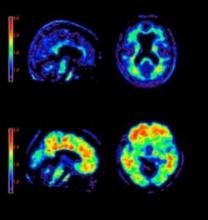

May 7, 2012 — Wide Beam Reconstruction (WBR) reduces the required radiopharmaceutical dose and image acquisition time by 50 percent for diagnostic quality myocardial perfusion imaging (MPI) single photon emission computed tomography (SPECT), according to a new study published in the March/April 2011 issue of the Journal of Nuclear Cardiology.